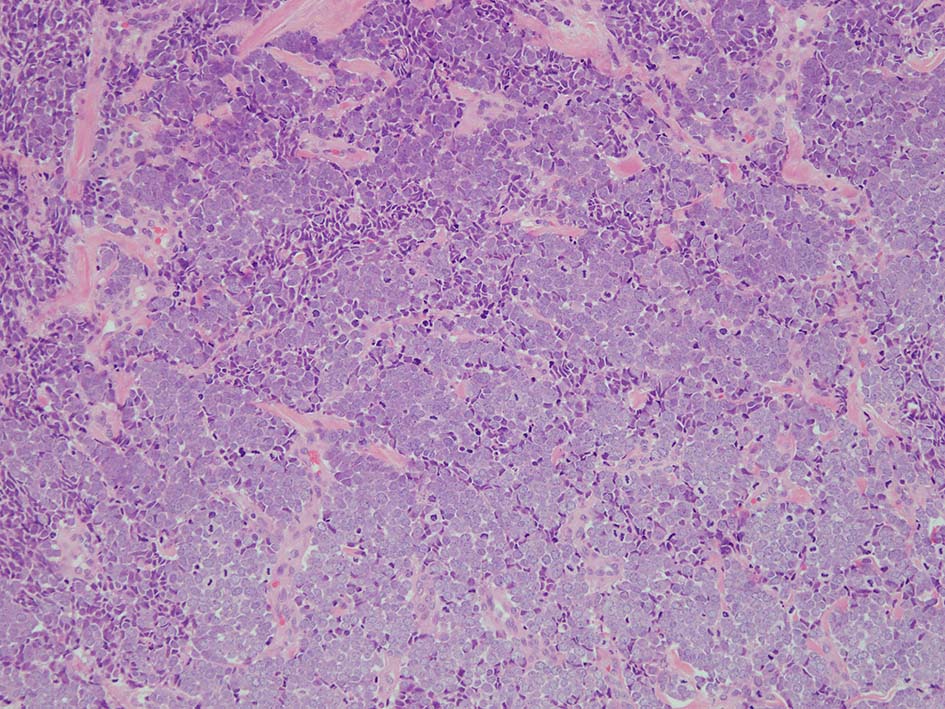

皮膚原発性Merkel細胞癌は 通常真皮を病変首座に増殖し, しばしば脂肪織まで浸潤する.

表皮とは連続性がなくGrenz zoneがみられるのが特徴であるが, 病理所見は多様であり, ときに表皮向性を示す症例やpagetoid patternを呈する症例もある.

典型的な腫瘍細胞は円形, 卵円形の比較的均一な形態で「salt-and-pepper」と称される微細顆粒状クロマチンを有する小型円形核をもつ. MCPyV陽性例が均一な小型円形核を呈する傾向があり, 陰性例では, 核多形性が目立つととする報告がある.

trabecular type, intermediate type, samll cell typeの3パターンの組織型に分類されているがしばしば混在している.

- intermediate typeではtrabecular, samll cell typeの中間の腫瘍細胞サイズを示す. 組織型としてはもっとも多い.

腫瘍内浸潤リンパ球/炎症細胞は多くの症例で認められる. リンパ球の腫瘍内浸潤は予後良好因子と報告されている. 16

HE

血管を間質にしてround cellsが索状に増殖する所見. rossett様配列がある. CK20は特徴的な dot-like patternを示す. クリックで大きな画像が見られます.